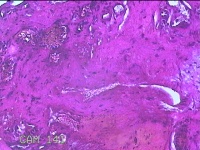

左眼翼状胬肉

性别

女

年龄

45岁

临床诊断

翼状胬肉

一般病史

反复双眼红伴异物感不适10余年。

标本名称

大体所见

灰白暗红色肿物0.3x0.2x0.1cm两个,表面糜烂。

符合。